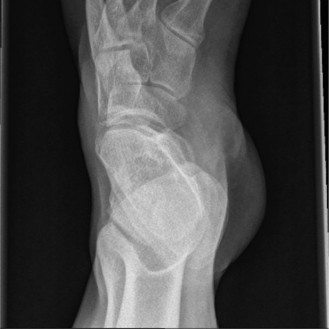

A 22-year-old female presents complaining of pain along the lateral border of her left foot. She has a known history of Charcot–Marie–Tooth disease (CMT) and a clinically evident pes cavus. Radiographs are obtained (Figs. 5–47 and 5–48).

Figure 5–48 AP weight-bearing radiograph of the foot.

The correct answer is (B). For reasons that are not entirely understood, muscles of the anterior compartment of the leg are selectively predisposed to weakness in CMT. The lateral compartment is also predisposed to weakness, but this specifically affects the peroneus brevis while sparing the peroneus longus. Thus, the anterior tibialis and peroneus brevis are weak while the posterior tibialis and peroneus longus remain strong, causing a force imbalance. This imbalance precipitates hindfoot varus through two mechanisms. First, the intact peroneus longus plantarflexes the first ray without the opposing dorsiflexion force normally provided by the anterior tibialis. The plantar-flexed first ray in turn drives hindfoot varus. Second, the intact posterior tibialis exerts an inversion force on the subtalar joint without the counterbalancing eversion force normally provided by the peroneus brevis. These two phenomena combine to create subtalar inversion and clinically apparent hindfoot varus.